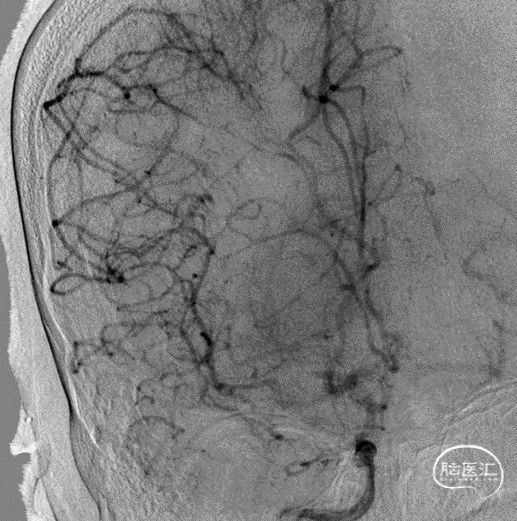

沿微导丝输送赛诺神畅 NOVA颅内药物球扩支架2.25*20mm支架到位,支架输送顺利,全过程无明显张力变化。

6atm缓慢扩张释放支架。

释放支架后造影见支架中段稍有残留狭窄,以8atm缓慢再扩张,残留狭窄消失。

最后工作位造影和正侧位造影,右侧大脑中动脉区域血流恢复,灌注满意。